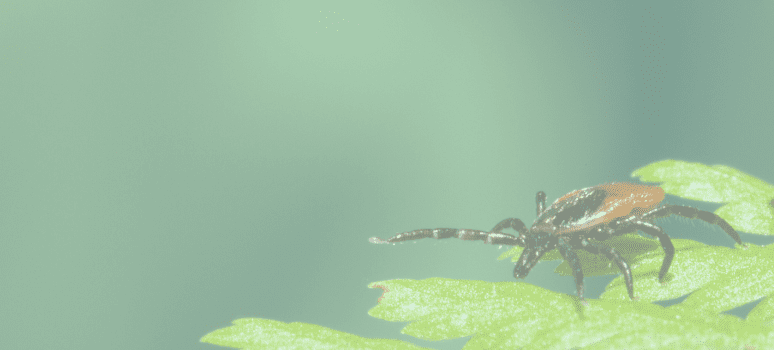

El Lyme en España es una enfermedad bastante desconocida y cuya dificultad de diagnóstico puede complicar la vida de quien

A la enfermedad de Lyme se la conoce como la gran imitadora. La sintomatología que presenta coincide en muchas ocasiones

La enfermedad de Lyme está cerca de ser endémica en muchas regiones de Europa. Sin embargo, no hay un criterio